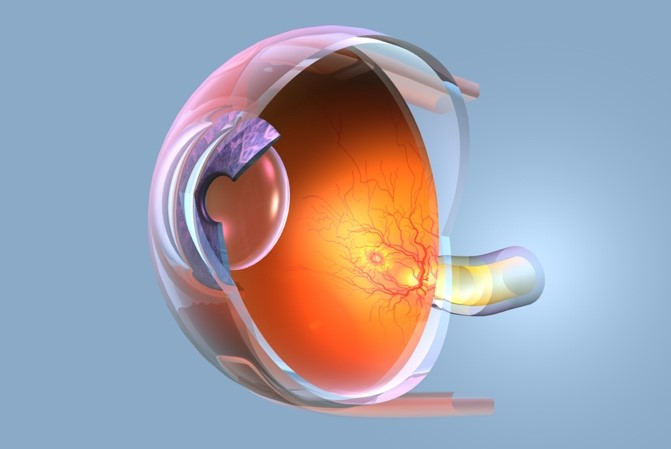

黄斑变性的病理生理机制

眼睛是心灵的窗户,但如果这扇窗户开始"生锈",那可就麻烦了。 今天我们要聊的黄斑变性,就是让这扇窗户逐渐失去光彩的"罪魁祸首"。 别担心,虽然听起来有点吓人...

黄斑变性的疾病概述与定义

黄斑变性虽然会对生活质量造成一定影响,但通过合理的治疗、积极的康复训练和家庭支持,大多数患者还是能够保持相对独立和有质量的生活。 关键是要早发现、早治疗,不要...